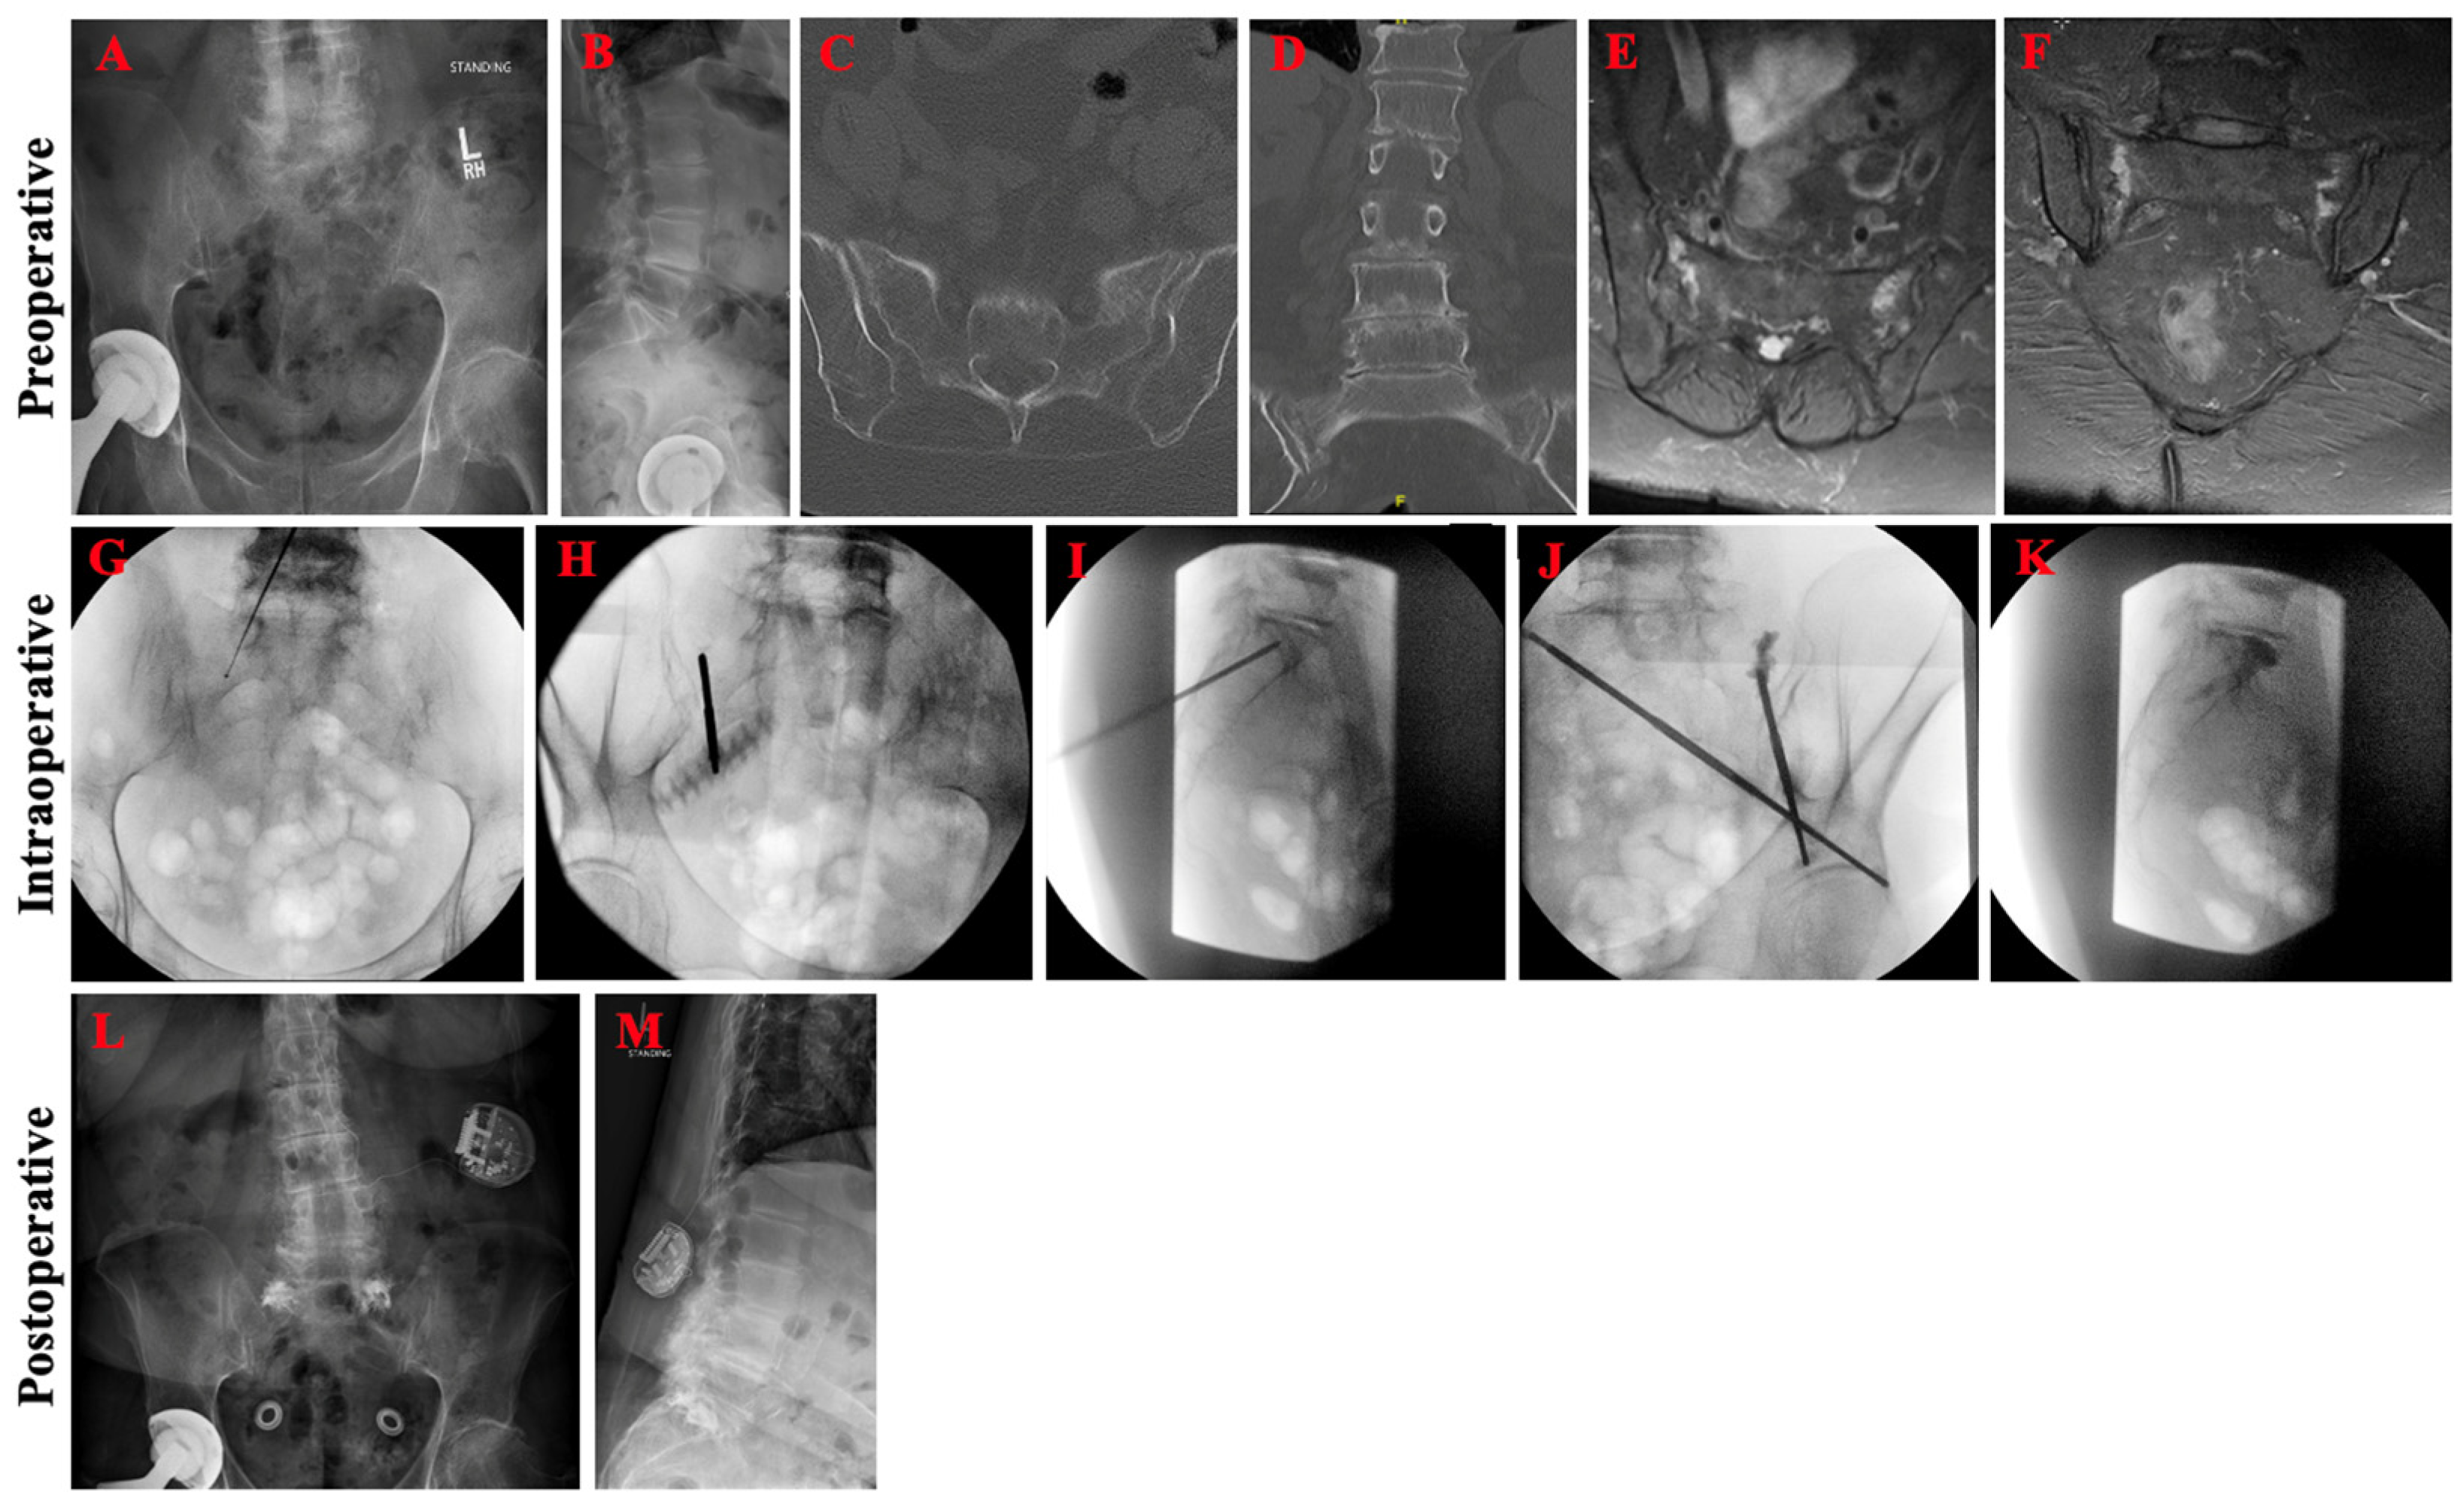

An 84-year-old female with a history of osteoporosis and chronic back pain presented with ten days of progressively worsening left-sided lower back and radicular leg pain, as well as difficulty with ambulation. She denied any recent history of trauma. She had previously trialed and failed conservative management with physical therapy, pain medications, and epidural steroid injections. Four-view lumbosacral spine radiographs demonstrated dynamic spondylolitic changes of the L3–4 vertebrae (Figure 4A,B). Lumbosacral CT confirmed L3–4 dynamic spondylolisthesis and bilateral Bakker B1 sacral alar insufficiency fractures (Figure 4C,D). Lumbar and pelvic MRI redemonstrated CT findings and confirmed severe stenosis at the L3–4 level, consistent with her radicular leg symptoms. In addition to L3–L4 posterior lumbar decompression and fusion, bilateral sacroplasty through the bilateral long-axis approach was pursued without cement extravasation or other complications (Figure 4G–K). Post-operatively, pelvic radiographs showed adequate cement deposition at the fracture site (Figure 4L,M). Patient had marked improvement in pain (ODI from 50 to 34, VAS from 9 to 4) and was able to mobilize independently on post-operative day one.

Figure 4.

Pre-operative, intraoperative, and post-operative imaging for patient case 2. Pre-operative anteroposterior (A) and lateral (B) lumbosacral spine radiographs demonstrated spondylosis of L3 over L4. Axial (C) and coronal (D) CT confirmed L3–4 dynamic spondylolisthesis and bilateral sacral alar insufficiency fractures. Axial I and sagittal (E,F) MRI STIR sequence of a related patient case showing edema at the fracture site. Intraoperative imaging during bilateral long-view sacroplasty demonstrated (G) successful ball tip probe cannulation of the right sacral ala without anterior penetration of the sacrum on anteroposterior inlet view, (H) Jamshidi cannulation down the right SI joint with no joint penetration on 25° right oblique view, (I) Jamshidi directed towards the anterior vertebral body with appropriate trajectory on lateral view, (J) cement filling the left sacral ala without joint or foraminal penetration on left oblique view, and (K) no final anterior or superior extravasation of cement on lateral view. Post-operative anteroposterior (L) and lateral (M) lumbosacral spine radiographs re-demonstrated spondylosis of L3 over L4 and good distribution of the cement without extravasation.